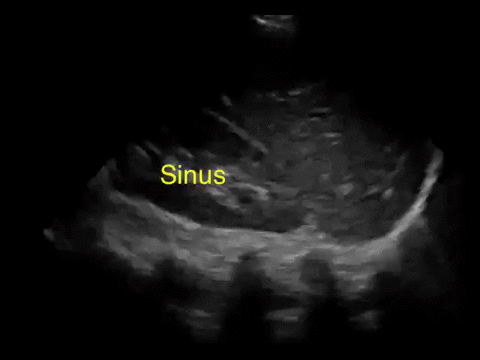

Point-of-care abdominal sonography is performed and the following representative image is obtained by examining the left flank.